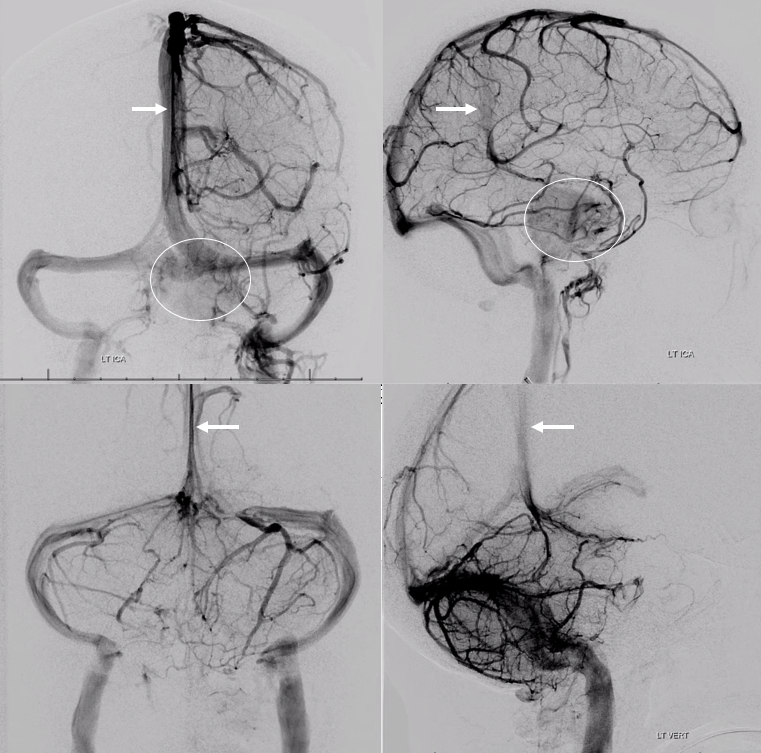

Sagittal Sinus Thrombosis — collaterals.

All of the above anatomic knowledge can become very useful in evaluation of venous thrombosis. Numerous collateral pathways develop in this setting attempting to compensate for the loss. The most dramatic cases usually involve the largest channel — the superior sagittal sinus. In this case, a man presented with what initially was thought to be vasculitis-related brain hemorrhage. Subsequent workup led to an angiogram, where sagittal sinus thrombosis with extensive trans-cerebral and trans-osseous emissary vein collateral channels was seen. In retrospect, these findings were present on the patient’s earlier contrast MRI. “Venovibe” or other contrast-enhanced MR venograms can very sensitive, particularly when interpreted with the appropriate index of suspicion. Noncontrast 2-D time of flight MRV I consider to be next to useless as a problem-solving technique. Any thin-slice postcontrast T1 study is vastly superior.